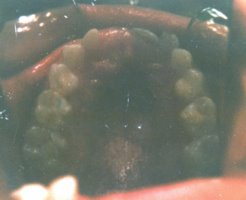

This patient had the beginnings of

crooked teeth. We now know that by utilizing modern orthodontic

techniques at as early an age as possible, many future problems can be

alleviated and in some cases even totally eliminated. For this 7 year

old girl, we used a fixed retainer called a Hyrax appliance for her